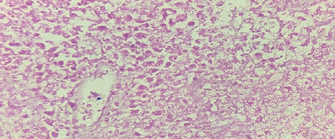

Spindle-shaped cells organized in fascicles, with hyperchromatic nuclei (Courtesy Dr. V. Penopoulos)